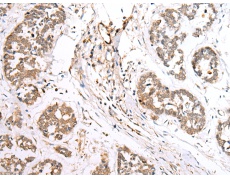

IHC positive control: |

Human tonsil and human esophagus cancer |

IHC Recommend dilution: |

30-150 |